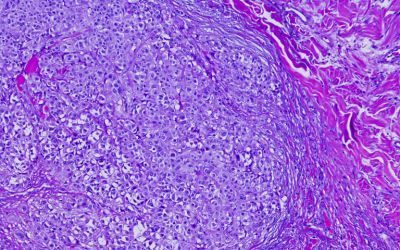

Si tratta del tumore della pelle più pericoloso ed è causato da un errore genetico acquisito nei melanociti, cioè nelle cellule che producono la melanina, che ne provoca una crescita incontrollata. Oltre alla predisposizione genetica, che riguarda circa il 20% dei casi, tra i fattori che inducono l’evoluzione maligna delle cellule è importante l’esposizione ai raggi UV. In seguito alla conferma della diagnosi, il trattamento dipende dal tipo di tumore, dallo stadio e dalla sede di insorgenza. L’approccio tipico prevede l’asportazione chirurgica, a cui possono essere associate altre terapie: fotodinamica, radioterapia, immunoterapia, farmaci personalizzati.